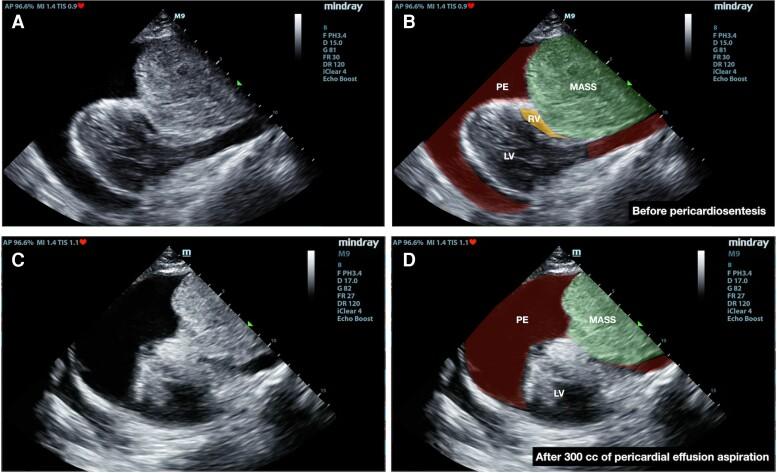

CASE SUMMARY

A 21-year-old male presented to the emergency department (ED) with breathlessness and hypotension. Bedside focused cardiac ultrasound revealed cardiac tamponade which was made worse with an anterior mediastinal mass compressing the right heart chambers. The patient was intubated for respiratory failure, following which an ultrasound-guided pericardiocentesis was performed. Unexpectedly, his hemodynamic status worsened after aspiration of 1000 mL of pericardial fluid. A repeat focused cardiac ultrasound showed reduced pericardial effusion, but worsening of right heart chambers compression by the mediastinal mass. Re-expansion of the pericardium space with 600 mL of normal saline improved the patient's vital signs, and reduced the right heart compression. Computed tomography was deferred due to the patient's hemodynamic instability. Despite resuscitation with fluids and initiation of vasopressor, the patient's condition deteriorated. He succumbed to his illness due to obstructive shock causing multi-organ failure. The autopsy showed a large anterior mediastinal mass, and histopathological examination confirmed the diagnosis of lymphoma.

一名21岁男性因呼吸困难和低血压被送往急诊科。床旁心脏超声检查显示存在心脏压塞,且前纵隔肿物压迫右心腔使病情加重。患者因呼吸衰竭行气管插管,随后进行了超声引导下的心包穿刺术。出乎意料的是,抽出1000毫升心包积液后,他的血流动力学状态恶化。再次进行的床旁心脏超声检查显示心包积液减少,但纵隔肿物对右心腔的压迫加重。注入600毫升生理盐水使心包腔重新扩张,改善了患者的生命体征,并减轻了对右心的压迫。由于患者血流动力学不稳定,计算机断层扫描检查被推迟。尽管进行了液体复苏并开始使用血管升压药,但患者的病情仍恶化。他因梗阻性休克导致多器官衰竭而死亡。尸检发现一个巨大的前纵隔肿物,组织病理学检查确诊为淋巴瘤。